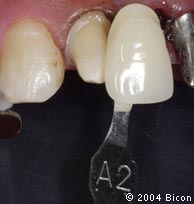

43. | 在黑色背景下比色并数码成像,以便于制作美观的义齿。 |